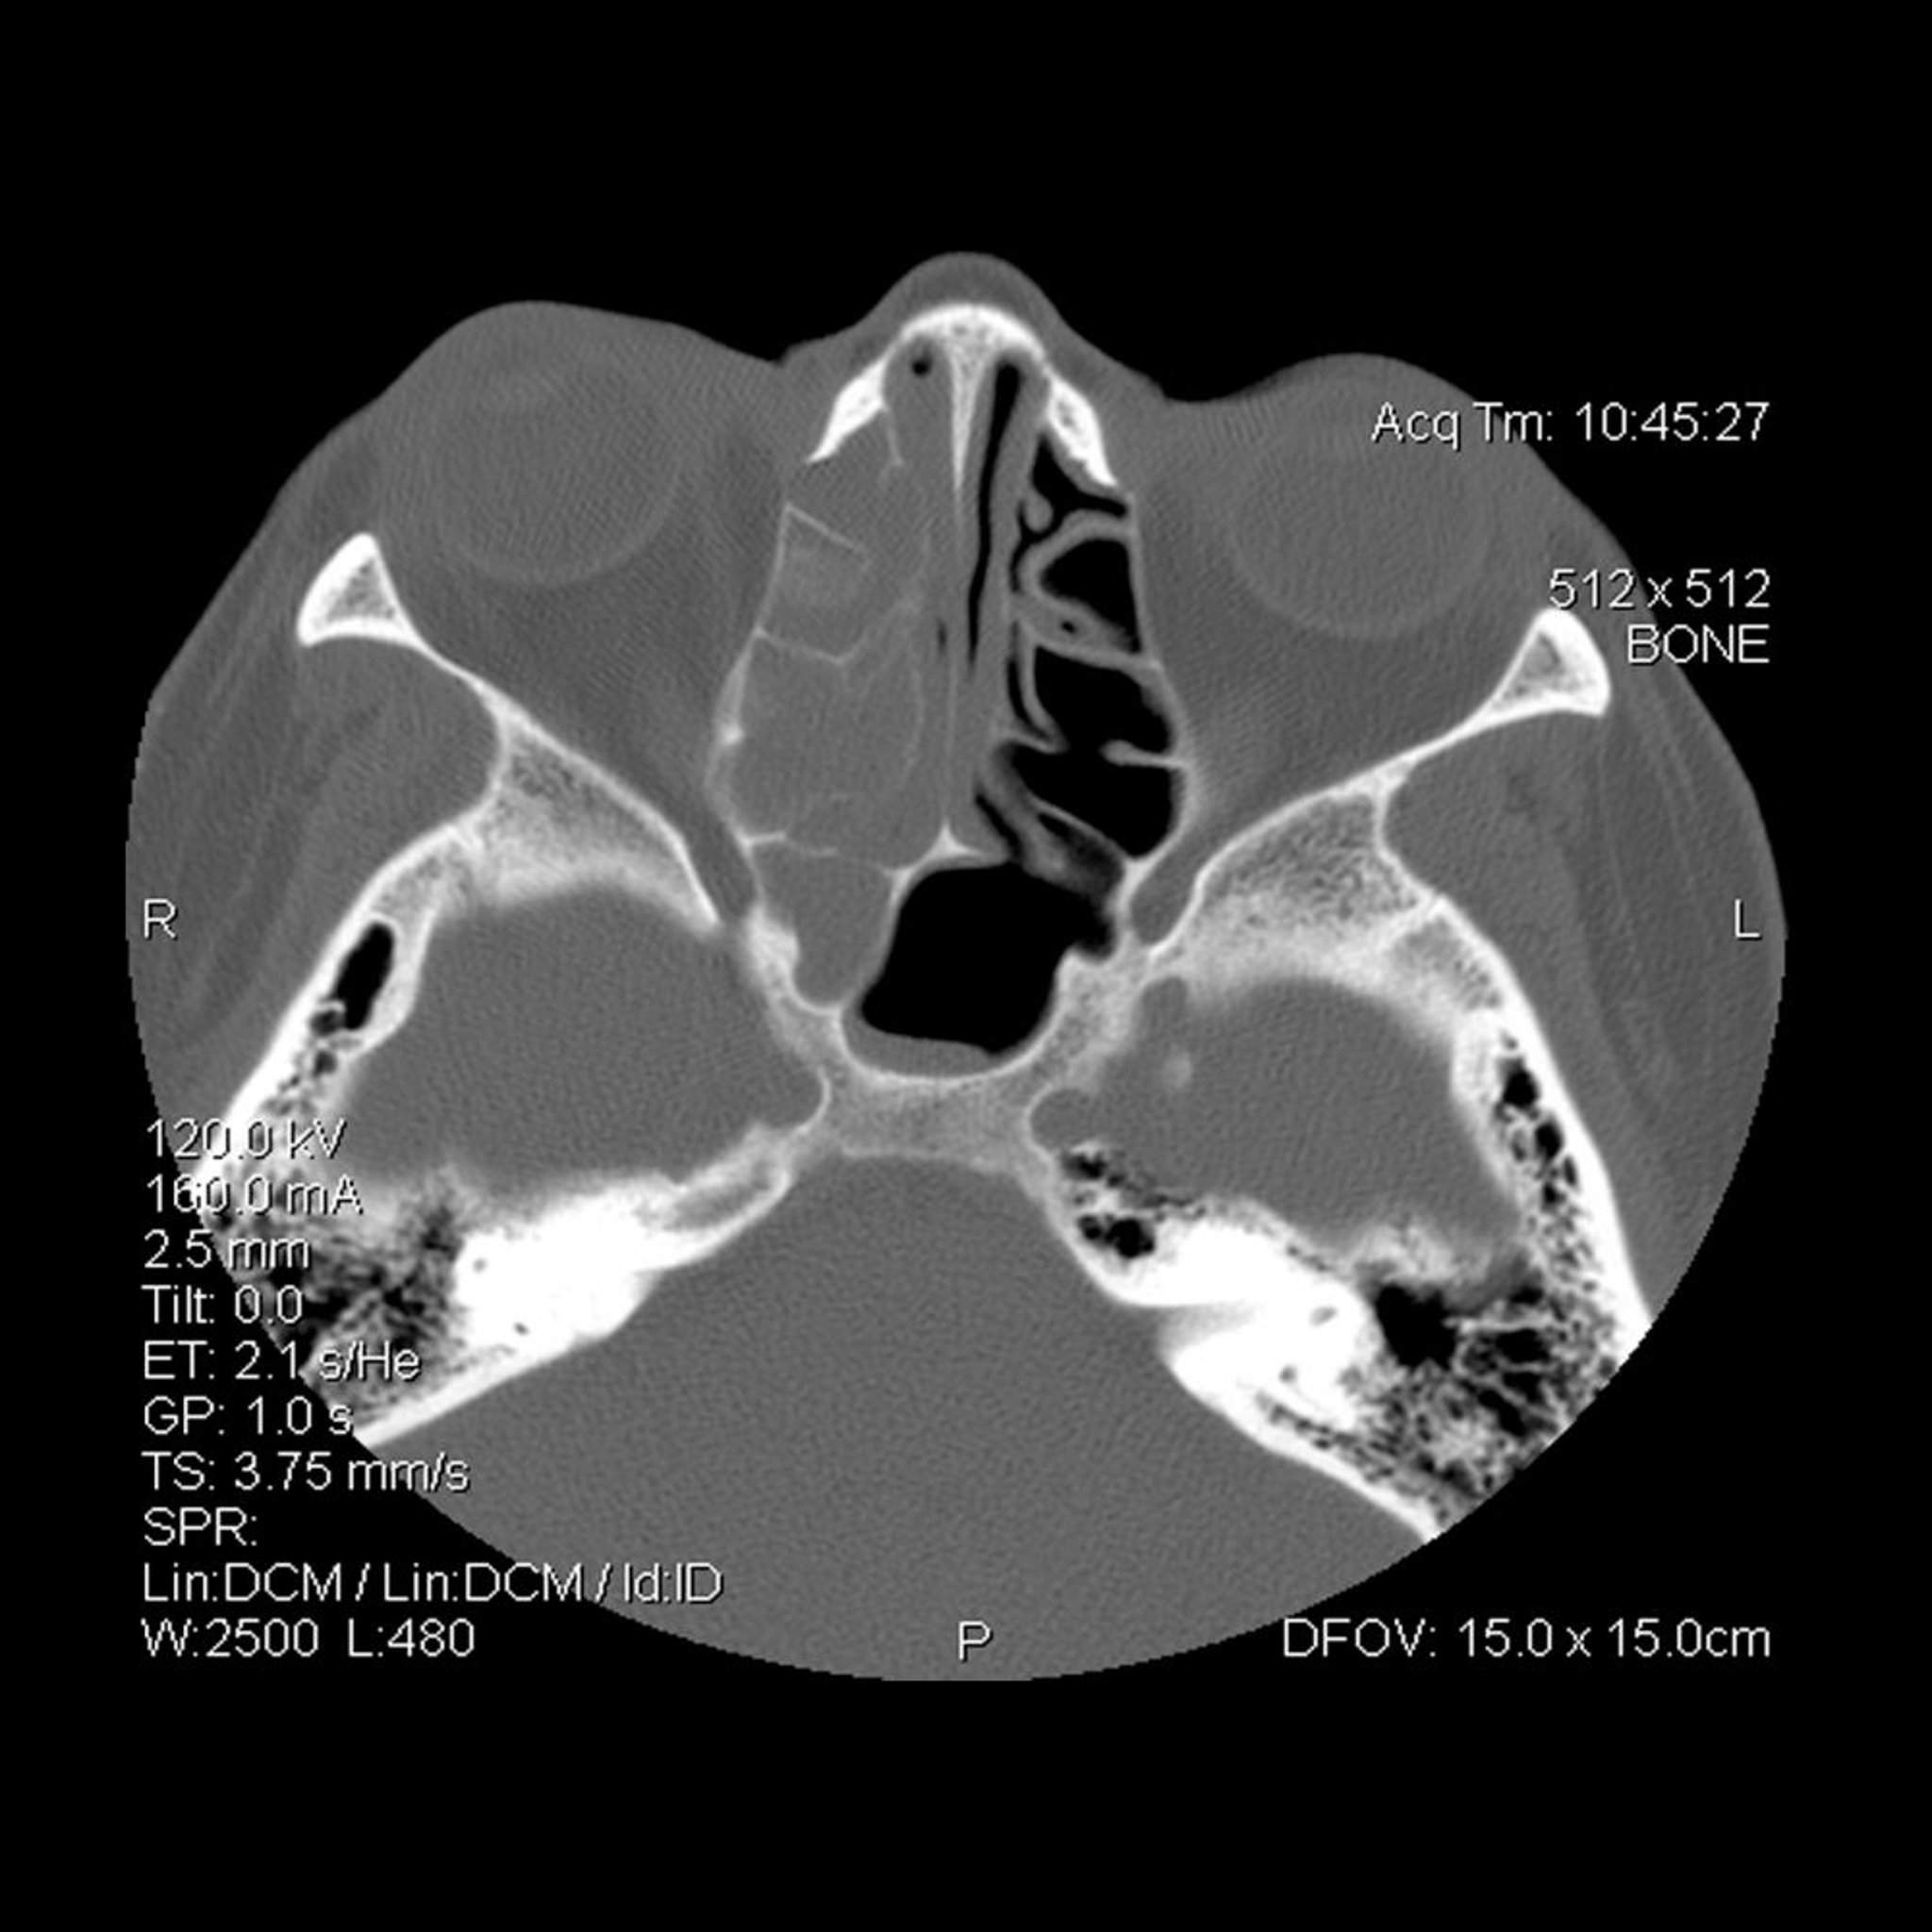

Opacificação do seios (à esquerda do observador) etmoidais e esfenoidais direitos.

Sinusite